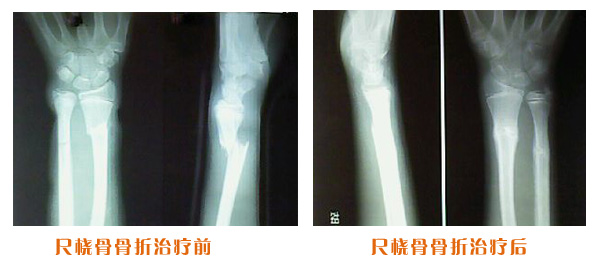

肥城市安駕莊梁氏骨科醫(yī)院是一所以梁氏手法正骨配合膏藥為特色的現(xiàn)代化專科醫(yī)院。

梁氏骨科術(shù)始創(chuàng)于清雍正年間,歷經(jīng)八代,至今已有三百年歷史。據(jù)1929年泰安縣志載“梁瑞圖先生,字增生,號蓮峰,安駕莊人,精岐黃并發(fā)明接骨,凡跌打車凡跌打車軋皮不破而碎骨者......【詳細(xì)】 |